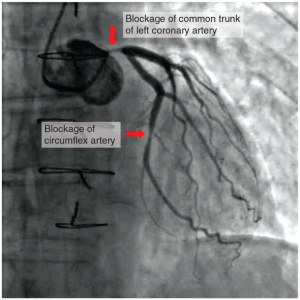

black and white image of Atherosclerotic coronary arteries

Figure 6.1.15. Atherosclerotic coronary arteries. In this coronary angiogram (X-ray), the dye makes visible two occluded coronary arteries. Such blockages can lead to decreased blood flow (ischaemia) and insufficient oxygen (hypoxia) delivered to the cardiac tissues. If uncorrected, this can lead to cardiac muscle death (myocardial infarction).

Coronary artery disease is the leading cause of death worldwide. It occurs when the build-up of plaque—a fatty material including cholesterol, connective tissue, white blood cells, and some smooth muscle cells—within the walls of the arteries obstructs the flow of blood and decreases the flexibility or compliance of the vessels. This condition is called atherosclerosis, a hardening of the arteries that involves the accumulation of plaque. As the coronary blood vessels become occluded, the flow of blood to the tissues will be restricted, a condition called ischaemia that causes the cells to receive insufficient amounts of oxygen, called hypoxia. Figure 6.1.15 shows the blockage of coronary arteries highlighted by the injection of dye. Some individuals with coronary artery disease report pain radiating from the chest called angina pectoris, but others remain asymptomatic. If untreated, coronary artery disease can lead to MI or a heart attack.